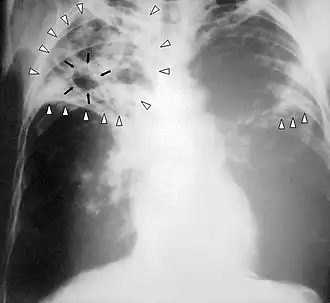

| Chest X-ray of a person with advanced tuberculosis: Infection in both lungs is marked by white arrow-heads, and the formation of a cavity is marked by black arrows. | |